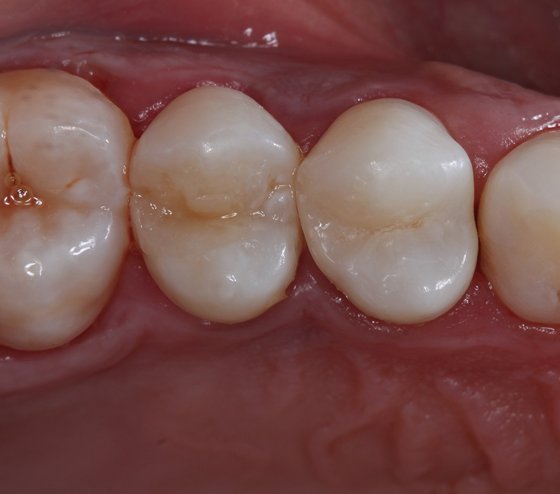

Initial situation (occlusal view)

Initial situation. Occlusal view.